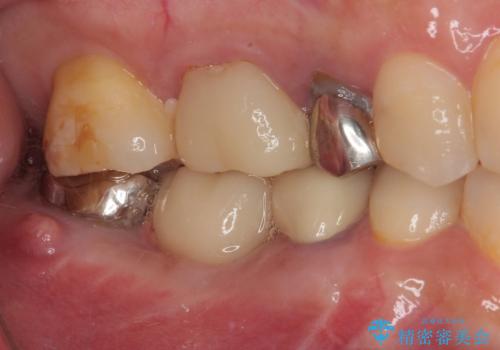

放置していたむし歯 抜歯即時埋入インプラントによる補綴治療

- むし歯を放置したままで、インプラント治療を希望して来院された患者様です。

左右ともにインプラントが必要な状態でした。

左下小臼歯は根管治療で対応する予定でしたが、診断のために歯肉を開いたところ頬側に垂直破折が認められたため、抜歯即時埋入インプラントによる補綴治療を選択することとしました。

右下は大臼歯部の歯は抜歯即時埋入インプラントにて、手前の歯は保存して補綴治療を行うこととしました。

インプラント埋入時に十分な安定値を得ることができたため、速やかに仮歯を装着し、最小限の通院回数で治療を終えることができました。